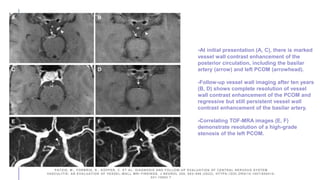

-At initial presentation (A, C), there is marked

vessel wall contrast enhancement of the

posterior circulation, including the basilar

artery (arrow) and left PCOM (arrowhead).

-Follow-up vessel wall imaging after ten years

(B, D) shows complete resolution of vessel

wall contrast enhancement of the PCOM and

regressive but still persistent vessel wall

contrast enhancement of the basilar artery.

-Correlating TOF-MRA images (E, F)

demonstrate resolution of a high-grade

stenosis of the left PCOM.